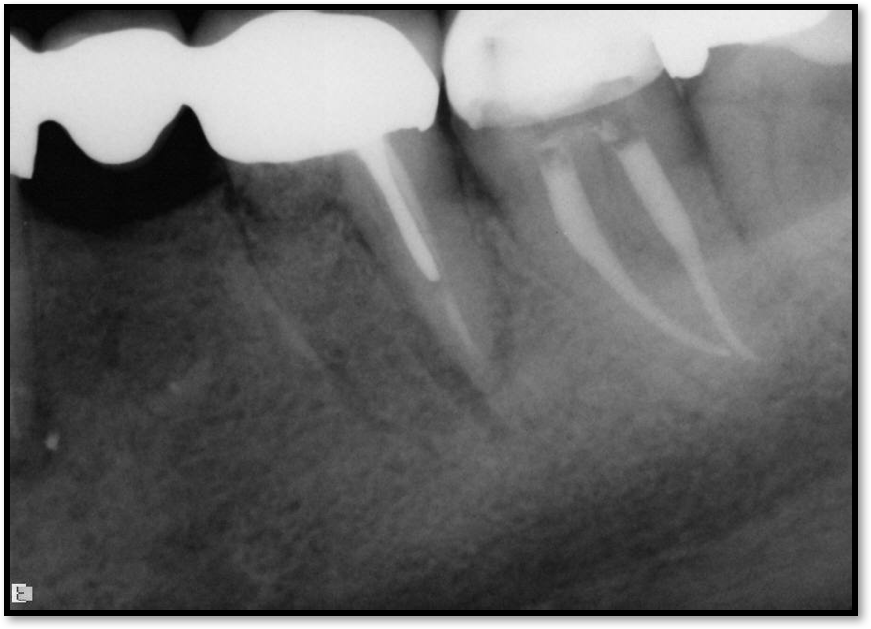

Occlusal Considerations

Occlusion is one of the most overlooked areas in endodontics; however, other than remaining structure, it is the most important factor.7 Patients who are heavy bruxers can cause the need for a root canal from the lateral forces. Patients who clench pose a different challenge with apical forces, yet the damage from both can be the same. Figure 7 shows a patient with bruxism. The patient had pain in response to hot and cold stimulus, and the clinicians needed a bitewing to determine which tooth was causing the pain. From the periapical (PA), it was clear that tooth No. 2 had a large problem, No. 3 had a crown, and No. 4 had a large restoration. Any of the three may have been the source of the problem.

With the bitewing shown in Figure 8, it became clear there was gross decay in tooth No. 3 that could not be seen on the PA, and there was a periodontal defect, a pulp stone, in No. 2. There was also a class V lesion revealing the bruxism, flat occlusion, multiple restorations in No. 30, a post in No. 31, and decay on No. 2 as well. The post in No. 31 was useless because when a post is placed, it must be the right length, width, and size. If the post is too short, there will be a greater fulcrum and the tooth will break. If it is too long, the clinician can break it by wedging it. If it is too short, it will not hurt the tooth, but it will not provide any valuable function. It is overall preferable to do posts in teeth having just single restorations rather than abutments for bridges because those teeth are already under greater force. If the technique is not performed correctly, iatrogenic issues may result.

Fig 7. Bruxism.

Figure 7

Fig 8. Bitewing revealed decay and other problems.

Figure 8